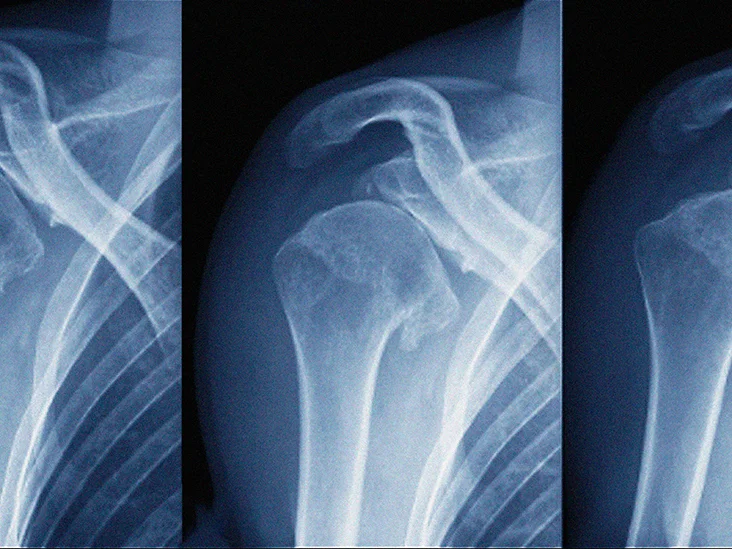

Anterior shoulder dislocation

Anterior dislocation of shoulder :

When dislocation occurs in anterior portion of the shoulder specially sub-glenoid,sub-coracoid, sub- clavicular is known as anterior shoulder dislocation.

3) Carry out an x ray to confirm the diagnosis.